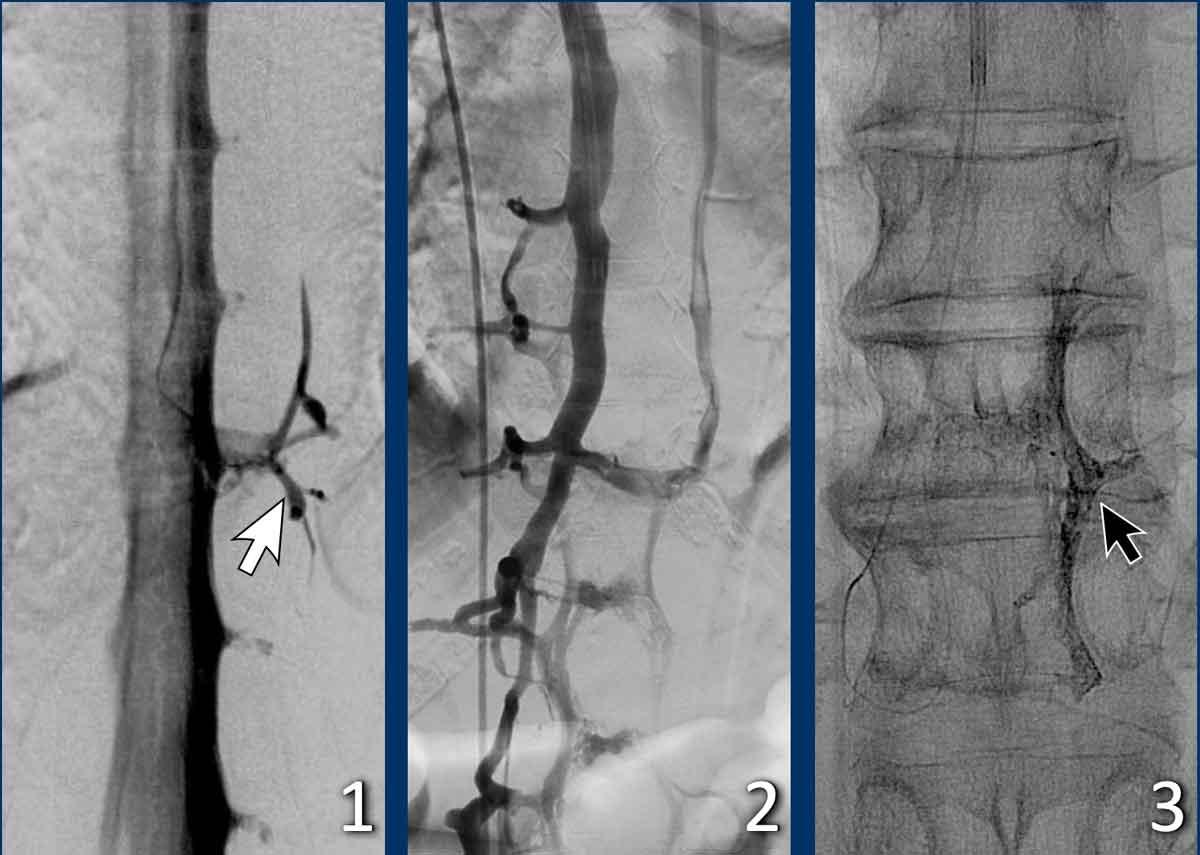

Cuối cùng, chụp tủy đồ xóa nền kỹ thuật số (digital subtraction myelography) được thực hiện (Courtesy René van den Berg).

Đầu tiên, tiến hành chọc dò thắt lưng.

Sau đó, bệnh nhân được đặt nằm nghiêng một bên và chụp ảnh với chùm tia nằm ngang trong khi thuốc cản quang được bơm vào và di chuyển theo hướng lên trên (xem video).

Khi bệnh nhân nằm nghiêng trái, không thấy bất thường nào.

Video này được ghi lại khi bệnh nhân nằm nghiêng phải.

Ở mức ngực thấp, có hiện tượng rò thuốc cản quang qua một rò dịch não tủy – tĩnh mạch.

Điều trị rò dịch não tủy – tĩnh mạch qua đường tĩnh mạch. Courtesy René van den Berg and Olvert Berkhemer

Các hình ảnh này của một bệnh nhân bị hạ áp lực nội sọ tự phát, có rò dịch não tủy – tĩnh mạch được điều trị qua đường tĩnh mạch.

Hình ảnh

- Rò dịch não tủy – tĩnh mạch (mũi tên).

- Điều trị bằng phương pháp can thiệp nội mạch và thuyên tắc qua đường tĩnh mạch.

- Khối vật liệu thuyên tắc có thể nhìn thấy trên hình ảnh không xóa nền bên phải.